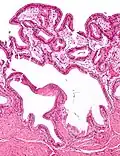

![]() Microfotografía de colesterolosis vesicular. H&E stain. | ||

En medicina, la colesterolosis vesicular es la acumulación focal de histiocitos espumosos (macrófagos) cargados de colesterol en la lámina propia de la vesícula biliar.[1]

A veces se llama vesícula biliar de fresa por el aspecto punteado de la superficie de la mucosa en un examen general, similar al que presentan las fresas. La colesterolosis está causada por una acumulación anormal de depósitos de ésteres de colesterol en macrófagos dentro de la lámina propia (células espumosas) y en el epitelio de la mucosa. La vesícula biliar puede estar afectada de forma localizada o de forma difusa. La forma difusa se presenta macroscópicamente como una mucosa roja brillante con motas amarillas (debido a los lípidos), de ahí la comparación con la fresa. No está ligada a la colelitiasis (cálculos vesiculares) ni a la colecistitis (inflamación de la vesícula biliar).[2]